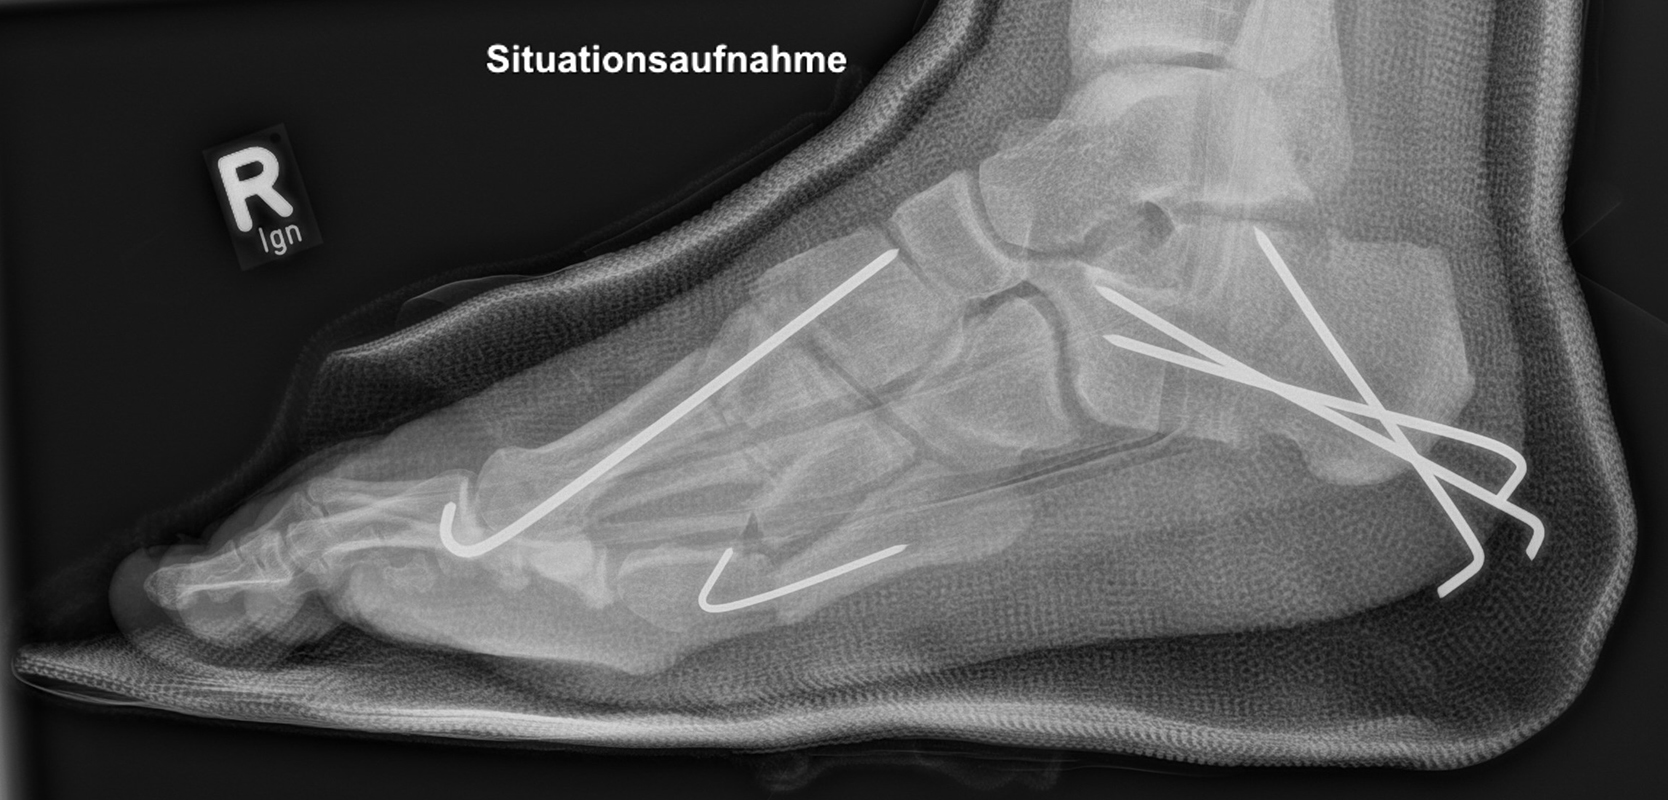

Calcaneus-Osteotomie

Die minimalinvasive Calcaneusverschiebeosteotomie bietet eindeutige Vorteile gegenüber dem offenen Verfahren, sodass wir bei Kindern und Jugendlichen nahezu keine offene Verschiebeosteotomie mehr durchführen. Am Calcaneus liegt die offene Wachstumsfuge dorsal. Bei der Durchführung müssen Schenkel der V-förmigen Osteotomie daher etwas steiler angelegt werden, in einem stumpfen Winkel (siehe Abb. 3 a-j). Für die Osteotomie liegen unsere Patienten auf dem Rücken und der BV wird für die exakte Seitaufnahme eingestellt. Der Fuß lagert auf einem hohen OP-Kissen und die Osteotomie kann bequem mit einem langen Kirschner-Draht und einem sterilen Stift angezeichnet werden (Abb. 15).

Damit lässt sich im Verlauf Röntgenstrahlung für die jungen Patienten vermeiden und die minimalinvasive Osteotomie kann sicher durchgeführt werden. Anschließend erfolgt die Verschiebung oder Impaktion. Ist ein Gleiten nach plantar oder cranial des distalen Fragmentes erwünscht, wird die Osteotomie schräg ohne V-Form entweder verlängernd oder verkürzend durchgeführt (Abb. 16).

Durch den knöchernen Defekt der Fräse gelingt die Verschiebung bei der minimalinvasiven Osteotomie im Fall von strukturell festen Klumpfüßen mit starkem Zug der verkürzten Achillessehne oder bei einer fixierenden spastischen Grunderkrankung einfacher gegenüber dem offen Verfahren. Ein weiteres Plus bei hyperaktiven Weichteilen ist die Vermeidung der ungewollten Cranialisierung des dorsalen Fragmentes durch die V-förmige Osteotomie (Abb. 16).

Die minimalinvasive Calcaneusverschiebeosoteotomie kommt somit in der Versorgung von kindlichen und jugendlichen Fußdeformitäten in einem weiten Erkrankungsspektrum zum Einsatz (Abb. 16):